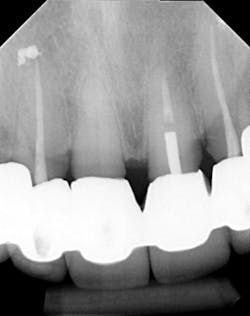

Dentition: Upper anterior splinted crowns had open margins and caries. Radiographs confirm decay, along with open margins (figures 6–11). Lower incisal anterior wear noted (figure 2).

Periodontium: Probing depths normal on all teeth, with some bleeding noted around the margins of the upper splinted crowns. Slight to moderate bone loss on lower anterior teeth.